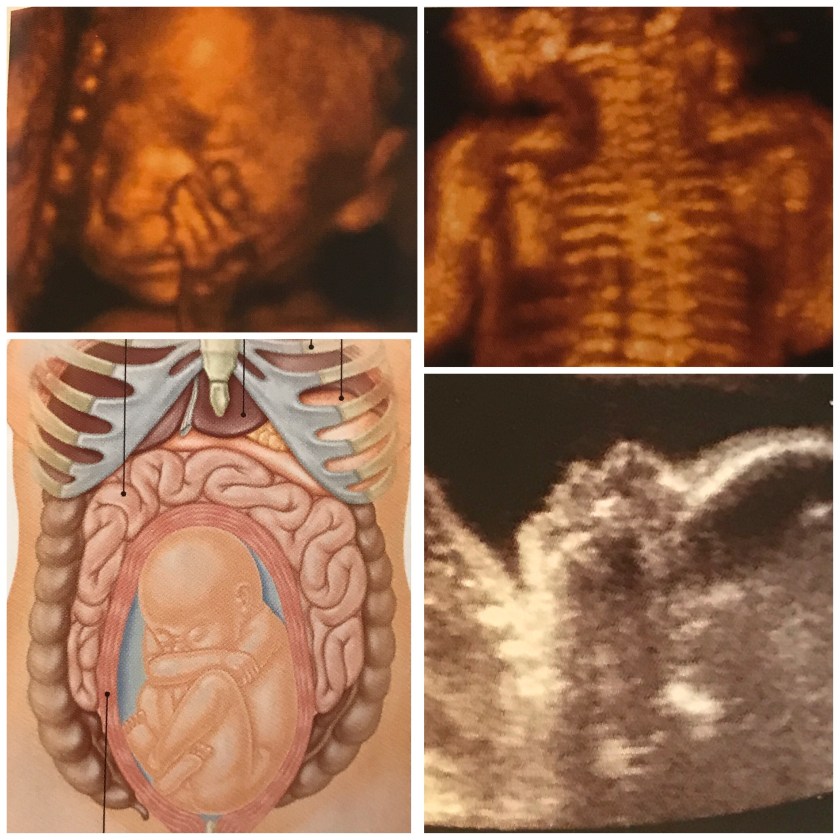

At 25 weeks our baby is putting on my baby body fat and his or her skin is becoming even less translucent.

As s/he grows, more room is taken up by his or her body causing more crowding near my rib cage. Baby is also growing hair in greater quantities, so that hair color and texture could be determined if it was visible now. In addition to baby growing my uterus is growing as well and is becoming the size of a small soccer ball.